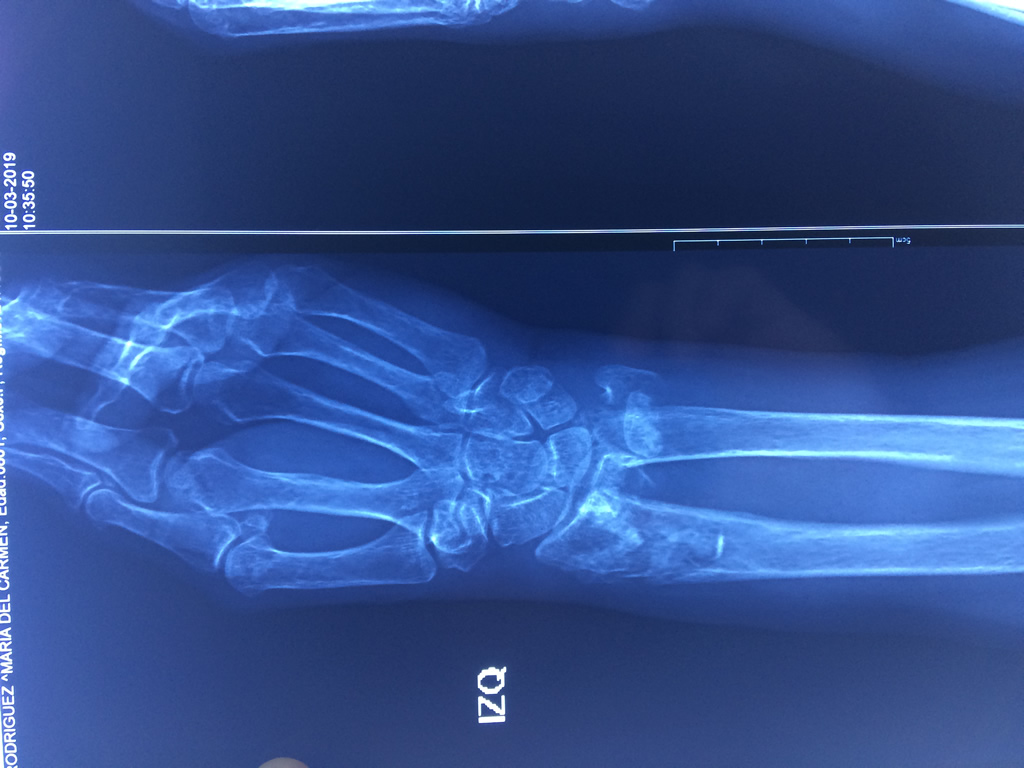

Los procedimientos más comunes en cirugía de la mano son aquellos destinados a reparar traumatismos, incluyendo lesiones de tendones, nervios, vasos sanguíneos, y articulaciones; huesos fracturados; y quemaduras, cortes, y otros daños de la piel.